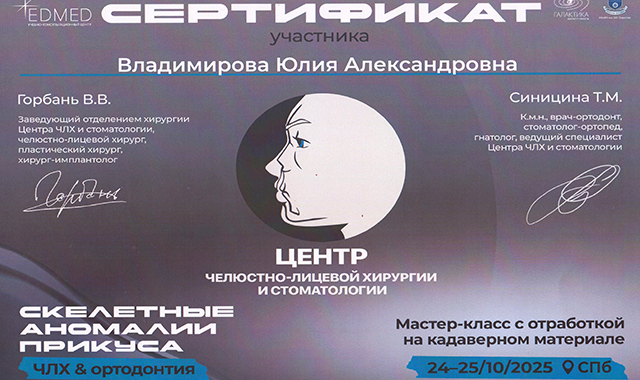

- Семинар: «Скелетные аномалии прикуса» Синицина Т.М., Горбань В.В., Санкт-Петербург, 2025